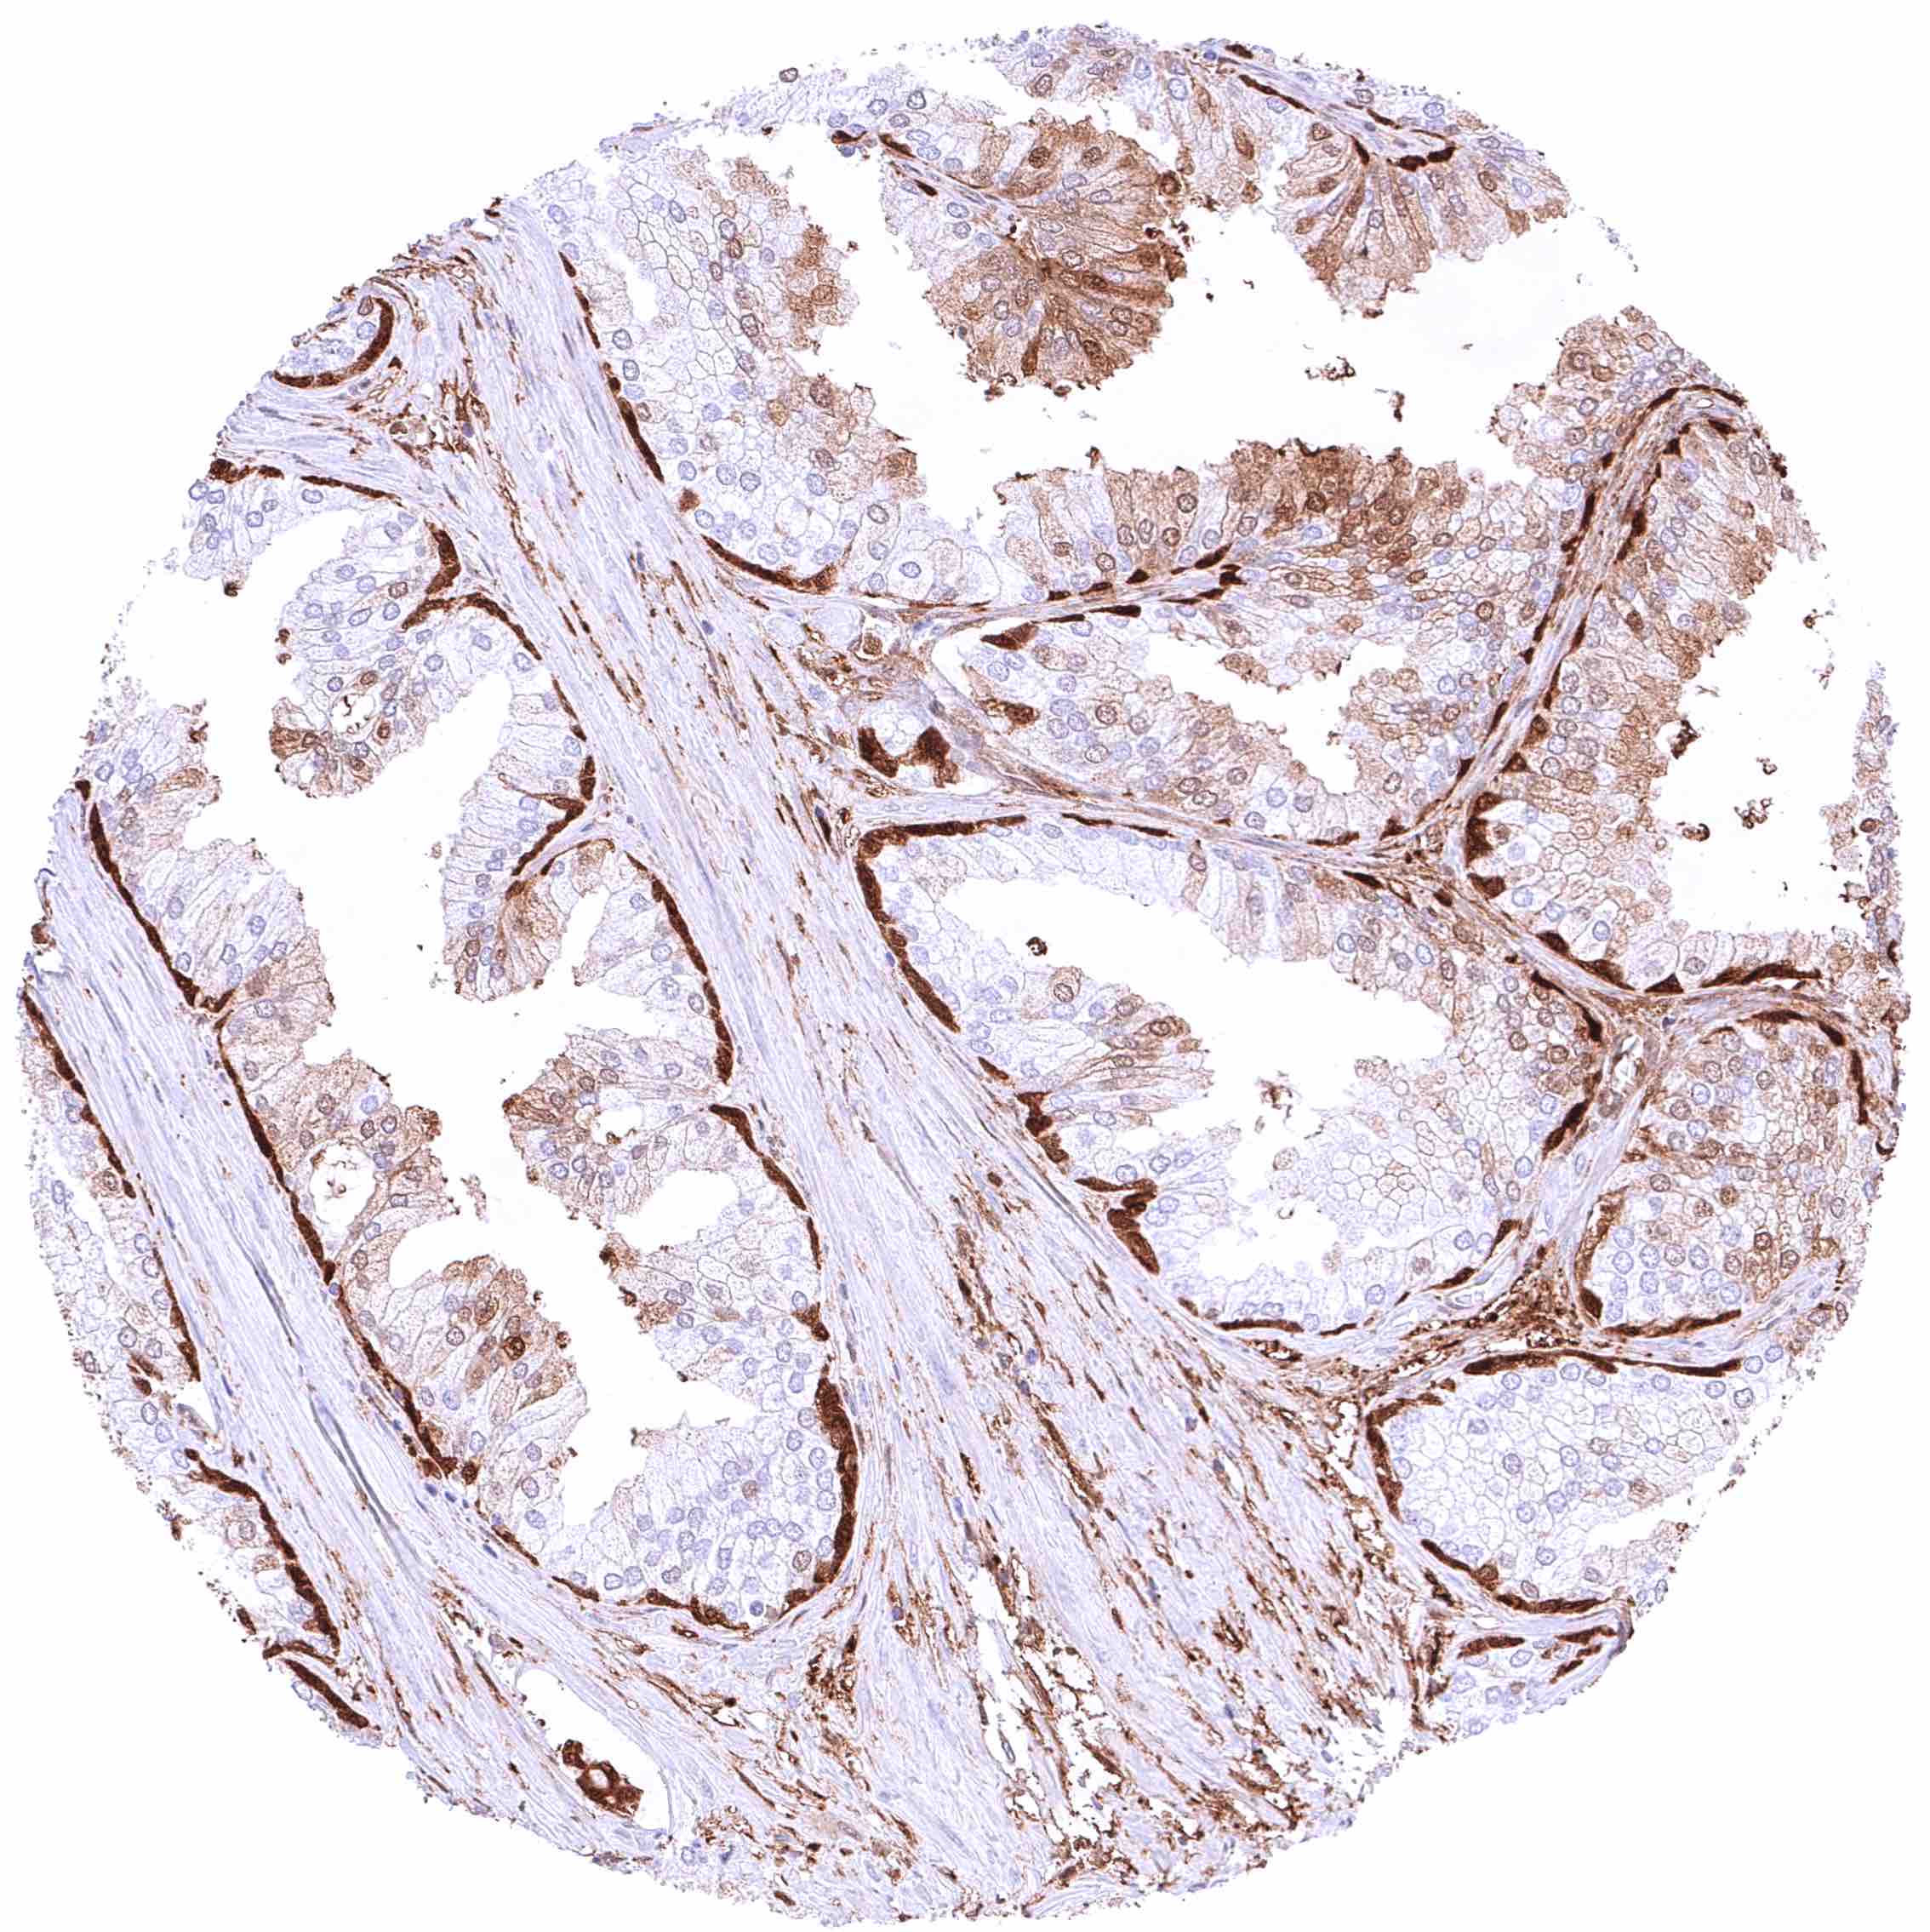

Prostate – Intense nuclear and cytoplasmic GSTP1 staining of basal cells while staining is faint or absent in acinar cells

Prostate – Intense nuclear and cytoplasmic GSTP1 staining of basal cells while staining is faint, weak or even absent in acinar cells